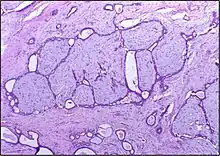

Macroscopic

Approximately 90% of fibroadenomas are less than 3 cm in diameter. However, these tumors have the potential to grow reaching a remarkable size, particularly in young individuals. The tumor is round or ovoid, elastic, and nodular, and has a smooth surface. The cut surface usually appears homogenous and firm, and is grey-white or tan in colour. The pericanalicular type (hard) has a whorly appearance with a complete capsule, while the intracanalicular type (soft) has an incomplete capsule.[11]

Histopathologic image of breast fibroadenoma showing proliferation of intralobular stroma compressing and distorting the epithelium. H&E stain. -